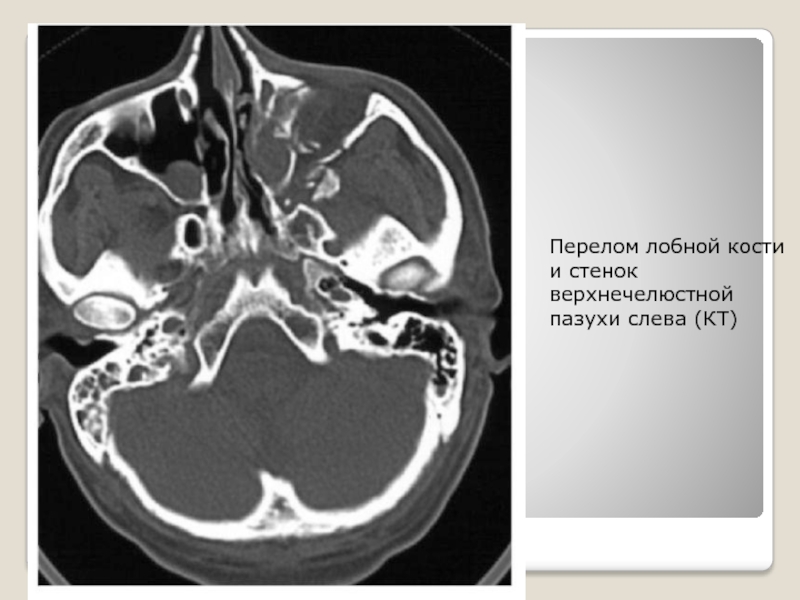

Слайд 18Перелом лобной кости и стенок верхнечелюстной пазухи слева (КТ)

Перелом лобной кости и стенок верхнечелюстной пазухи слева (КТ)